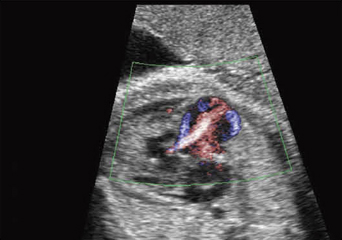

医療従事者の間で話題になっているのみならず,ママたちの書くブログにもNTの話題が載る。このことが胎児心疾患の診断時期に影響を与えた。羊水による染色体検査の実施を勧められている,あるいは自ら考えているママたちをカウンセリングするにあたって,胎児心疾患の存在,もしくは否定は重要な情報である。羊水による染色体検査は妊娠16週に実施されることが多いので,超音波による胎児臓器のスクリーニングもこれに合わせて行われることが多くなった。図5,6に示す症例は,NTが見つかり,引き続き胎児超音波精査を行ったところ,妊娠15週で両血管右室起始と診断された。染色体検査の結果はTrisomy18。

この時期の胎児心臓の観察では,経膣超音波と,経腹超音波の両方を使用するのが好ましい。ダイナミックフローのような,分解能に優れた血流表示が必須である。心臓が近くにあれば,経膣超音波の方が分解能に優れるが,胎児の左右の認識が困難なことがある。妊娠16週胎児心臓スクリーニングでの観察項目は,(1) 四腔断面,(2) 大動脈の起始部,(3) 肺動脈の起始部,(4) 両大血管の走行,(5) 大動脈アーチの追跡である。白黒画像とダイナミックフローの両方を使えば理解が得やすい。

![]() 図5 Trisomy18 この症例の頸部には多?胞なNTが観察された。 |

![]() 図6 Trisomy18 右室起始の大動脈を示す。妊娠15週の心臓スクリーニングで大動脈, 肺動脈とも右室起始(DORV)が認められた。羊水染色体検査の結果はTrisomy18と診断された。 |